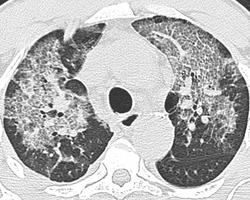

После внутривенного введения кокаина.

Имеются сообщения о поражении других органов и систем, в частности мозга и печени. При внутривенном употребления кокаина нередки инфекционные и эмболические осложнения. При курении сам наркотик или его примеси могут повреждать альвеолярный аппарат легких [8]. При вдыхании кокаина через нос может произойти перфорация носовой перегородки.